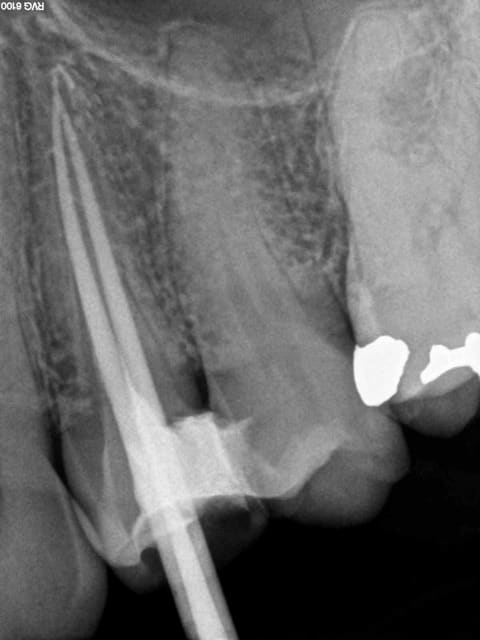

signes radios:espace desmodontal inf à 1mm

pas d'image apicale

lamina dura normal

pas de résorption apparente

obturation dense confinée à l'espace endo et

semblant atteindre la jonction cémento dentinaire(à un mm

de l'apex anatomique environ)